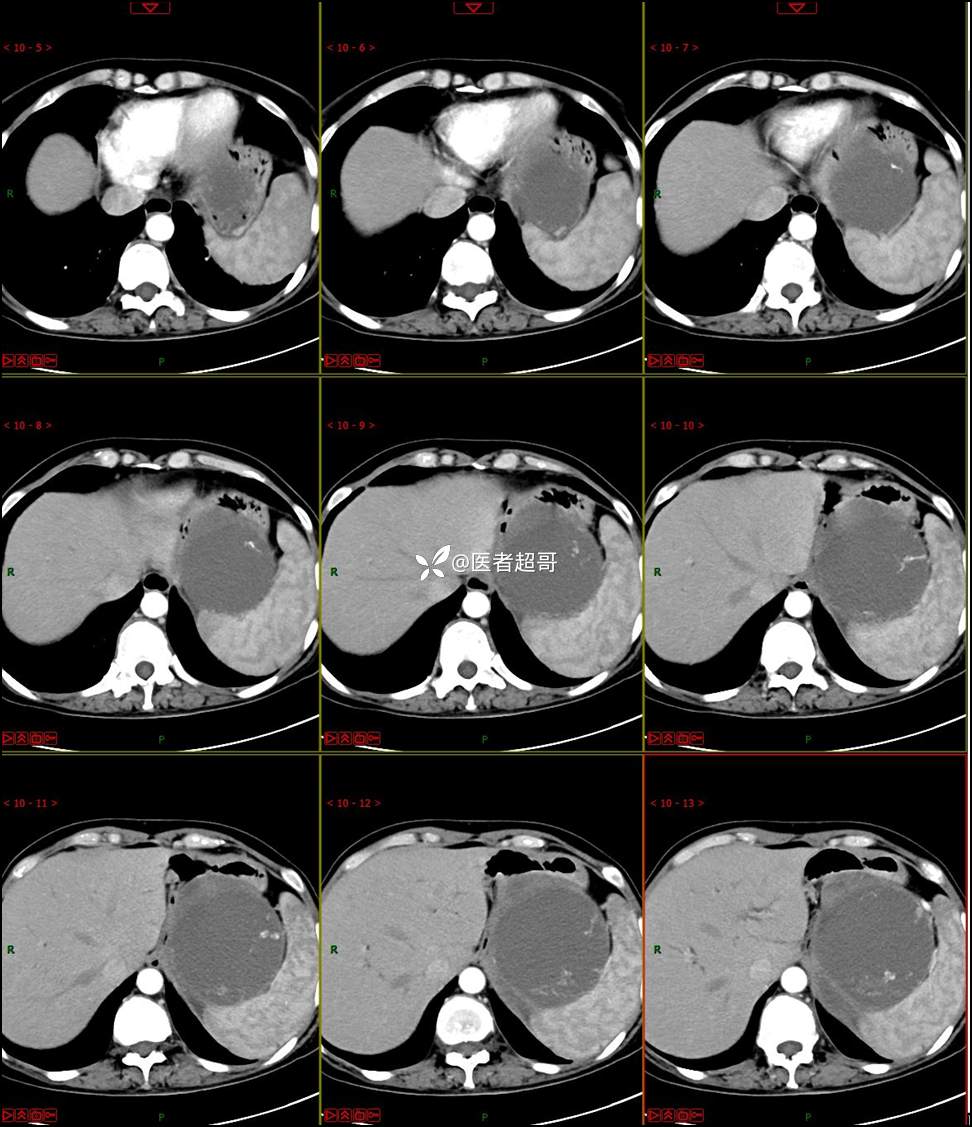

【影诊笔记768】肾脏肿瘤?肾上腺肿瘤?请诊断分析!

女 57岁 0200908 01

主 诉:发现左肾肿物7月余

现病史:患者7月前因左侧腹部疼痛不适,就诊市人民医院,行CT平扫:左侧肾上腺区混杂密度肿块,考虑肿瘤合并出血,行保守治疗后症状缓解出院,左侧下腹部及左侧髋部疼痛不适,无尿频、尿急、尿痛,无肉眼血尿,无寒战、发热,今患者为求进一步诊治,就诊我院,门诊以“左肾肿物”为诊断收入院,患者自发病以来,神志清,精神可,饮食睡眠可,小便如上述,大便正常,体重未见明显改变。